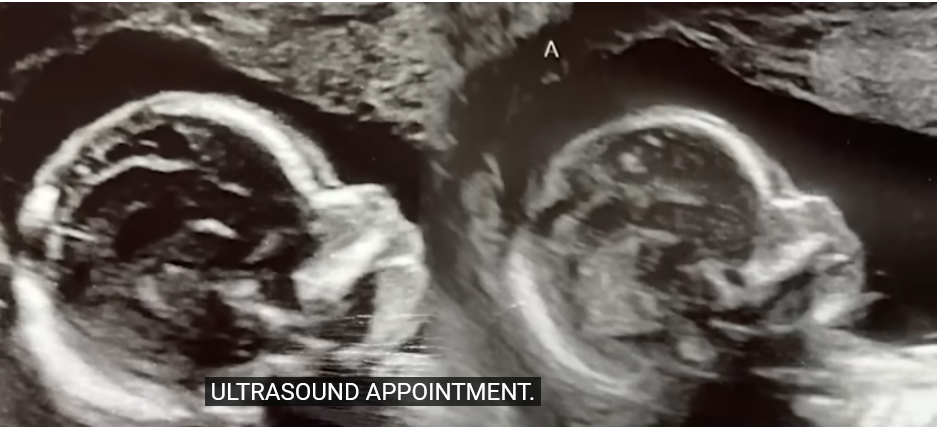

في الفيديو، ظهرت كيلسي وهي تجري فحصًا بالموجات فوق الصوتية، حيث ظهرت صور الجنينين في رحميها منفصلين. وبحسب الأطباء، فإن الحالة تُعرف باسم “الحمل المتزامن في رحمين منفصلين”، وهي حالة نادرة جدًا، حيث تحدث في حوالي 1% من جميع حالات الحمل.